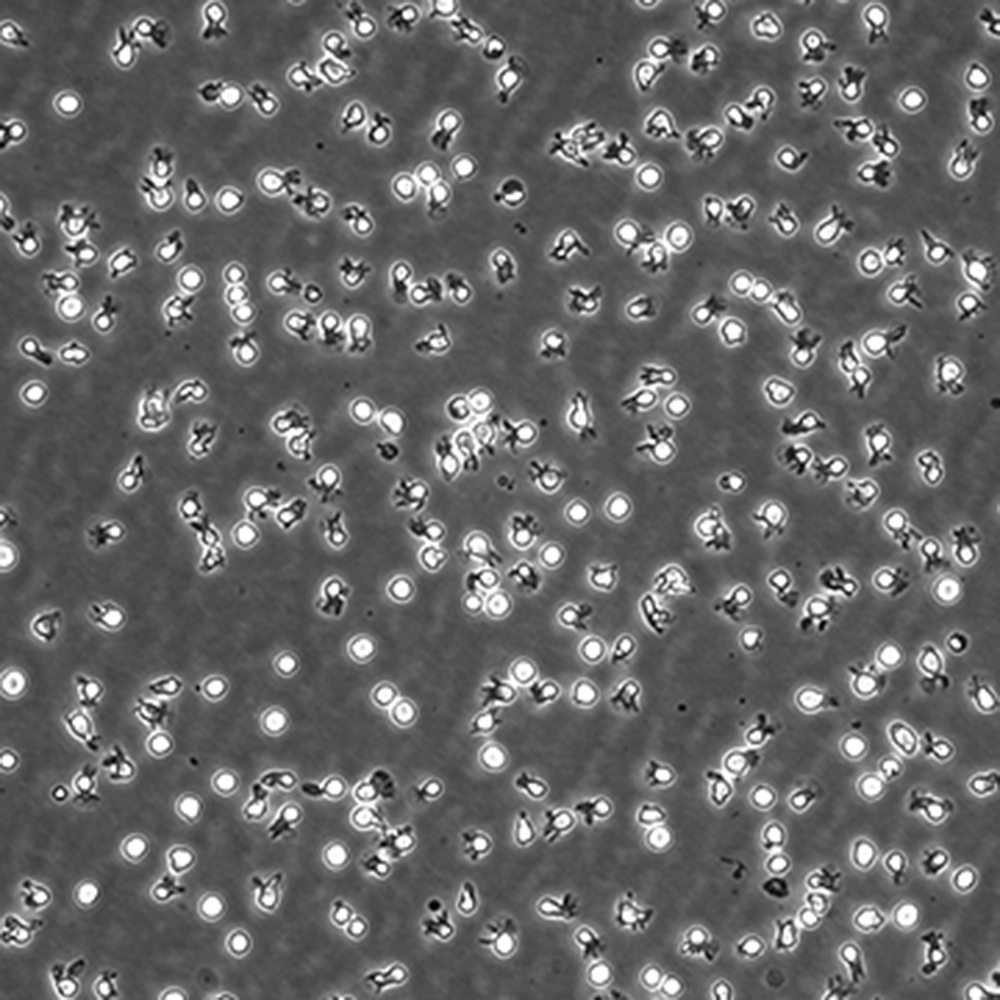

中文名稱 人彌漫大B細(xì)胞淋巴瘤細(xì)胞

生長(zhǎng)特性 懸浮